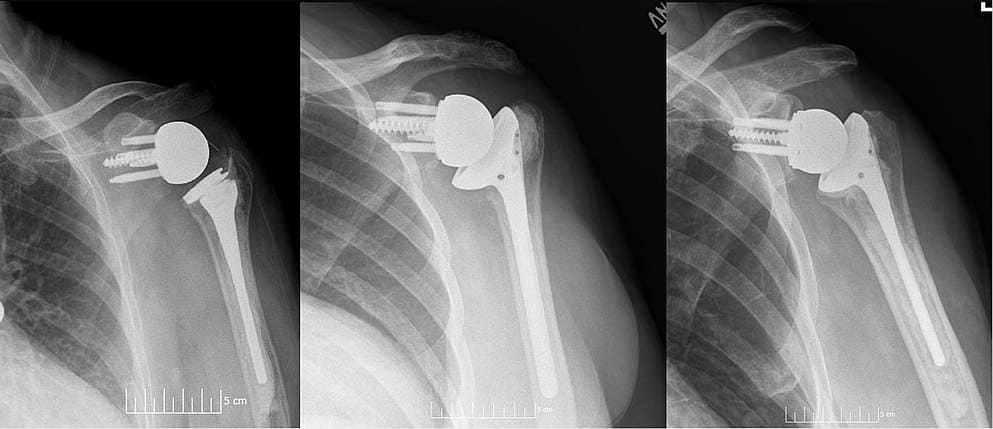

Reverse Shoulder Replacement Surgery

Reverse Shoulder Replacement Surgery is an advanced orthopedic procedure designed for patients suffering from severe shoulder damage, arthritis, or complex fractures where conventional treatments may not be effective. This surgery is especially beneficial for individuals with rotator cuff tear arthropathy, where the shoulder muscles are no longer functioning properly.

In this procedure, the normal structure of the shoulder joint is reversed. The ball and socket positions are switched, allowing the deltoid muscle to take over the function of the damaged rotator cuff. This helps restore shoulder movement, improve strength, and significantly reduce pain.